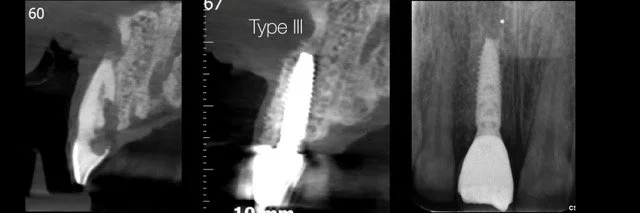

• Single implants in the esthetic zone.

• The importance of implant design, implant connection, abutment selection and treatment workflow.

• How to understand and develop the transmucosal contour around implants.

• Immediate, early, delayed or late implant?

• From tissue preservation to immediate loading protocols.